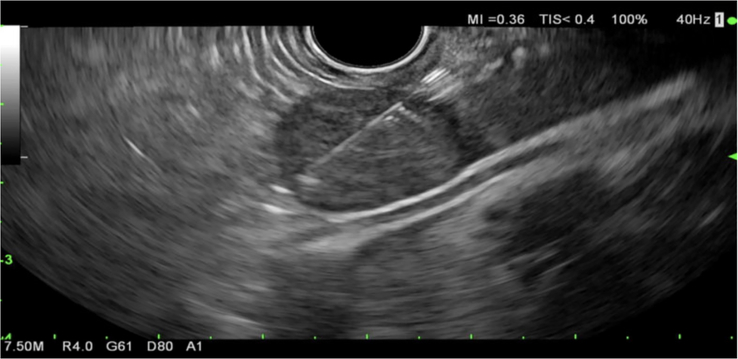

Abstract Image